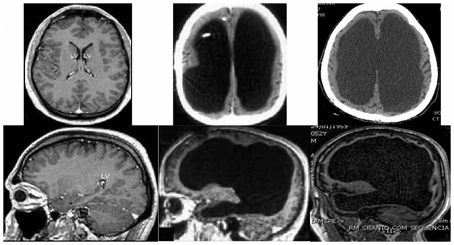

Bateson and Gluckman seem to accept Lorber's reduncy argument to the extent that we know that one part of the brain can sometimes accommodate to damage in another part, so the brain exhibits functional plasticity. So do Oliviera et al. (2102) in new studies from Brazil.

Fake adaptation from Feuillet et al. 2007 that DRF unknowingly uploaded

Brain scans of patients of Oliveira et al. Normal appearance (left). Abnormal appearance (middle and right). The middle patient is clinically normal, whereas the right patient has suffered "deep cognitive and motor impairment since childhood."(Reproduced under Creative Commons Licence)

However, it seems to me that the "plasticity" (or "brain resilience") explanation must have a limit. The drastic reduction in brain mass in these cases seems to demand an unimaginable  level of superplasticity. How much brain must be absent before we abandon the plasticity explanation and look for another explanation? Had I known of the hydrocephalus cases, I would have included them in the above paper, where I used, to support my case, the fact that a small minority of microcephalics have normal IQs. The wacky explanation I came up with (see above), seems no more wacky that the "plasticity" explanation.